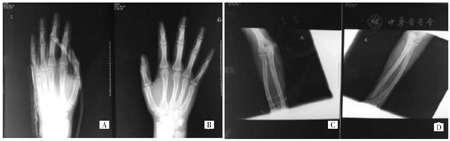

患者入院诊断为急性汞中毒、双上肢静脉炎,给予二巯基丙磺酸钠肌注驱汞、持续血浆吸附灌流(树脂灌流器HA330,珠海健帆生物科技有限公司)进一步清除体内汞成分。急诊全麻下行双上肢汞清除术+部分静脉切除术+负压封闭引流技术(VSD),术中右上肢透视定位,汞位于掌侧尺侧、背侧尺侧,走形沿贵要静脉,延伸至腕部,切开可见皮下变形的脂肪组织和炎性反应组织,有小汞珠散在溢出,整体切除静脉并将深筋膜连同变性脂肪一同切除。左上肢自肘掌侧至前臂尺侧,切除受污染的变性组织瓣,双上肢术后均给予VSD持续负压封闭引流。手术切除左手背污染的病变皮下组织,放置橡胶引流条。X线显示术后左手软组织下金属密度影较术前明显减少(图3A、图3B)。术后第8天再次给予透视定位下清除双上肢残存金属汞并继续给予VSD负压引流,复查X线双上肢残存汞近乎完全清除(图3C、图3D)。

A:左手掌;B:右手掌;C:左前臂及肘部;D:右前臂及肘部